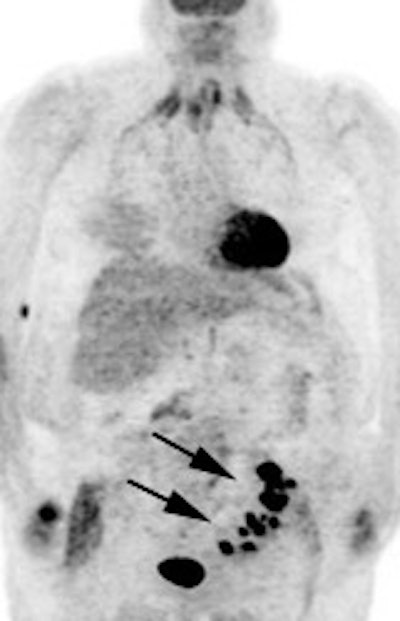

Genitourinary activity: The image below demonstrates activity within the collecting system of a transplanted kidney (black arrows). This should not be mistaken for an abnormality. |

|

Bladder cancer: Dilute urinary activity in this patient's bladder allowed accurate detection of their bladder cancer (white arrows on CT, black arrows on PET scan). In general, urinary excretion of FDG limits evaluation of urinary tract malignancies, however, hydration and diuresis can improve diagnostic accuracy. |